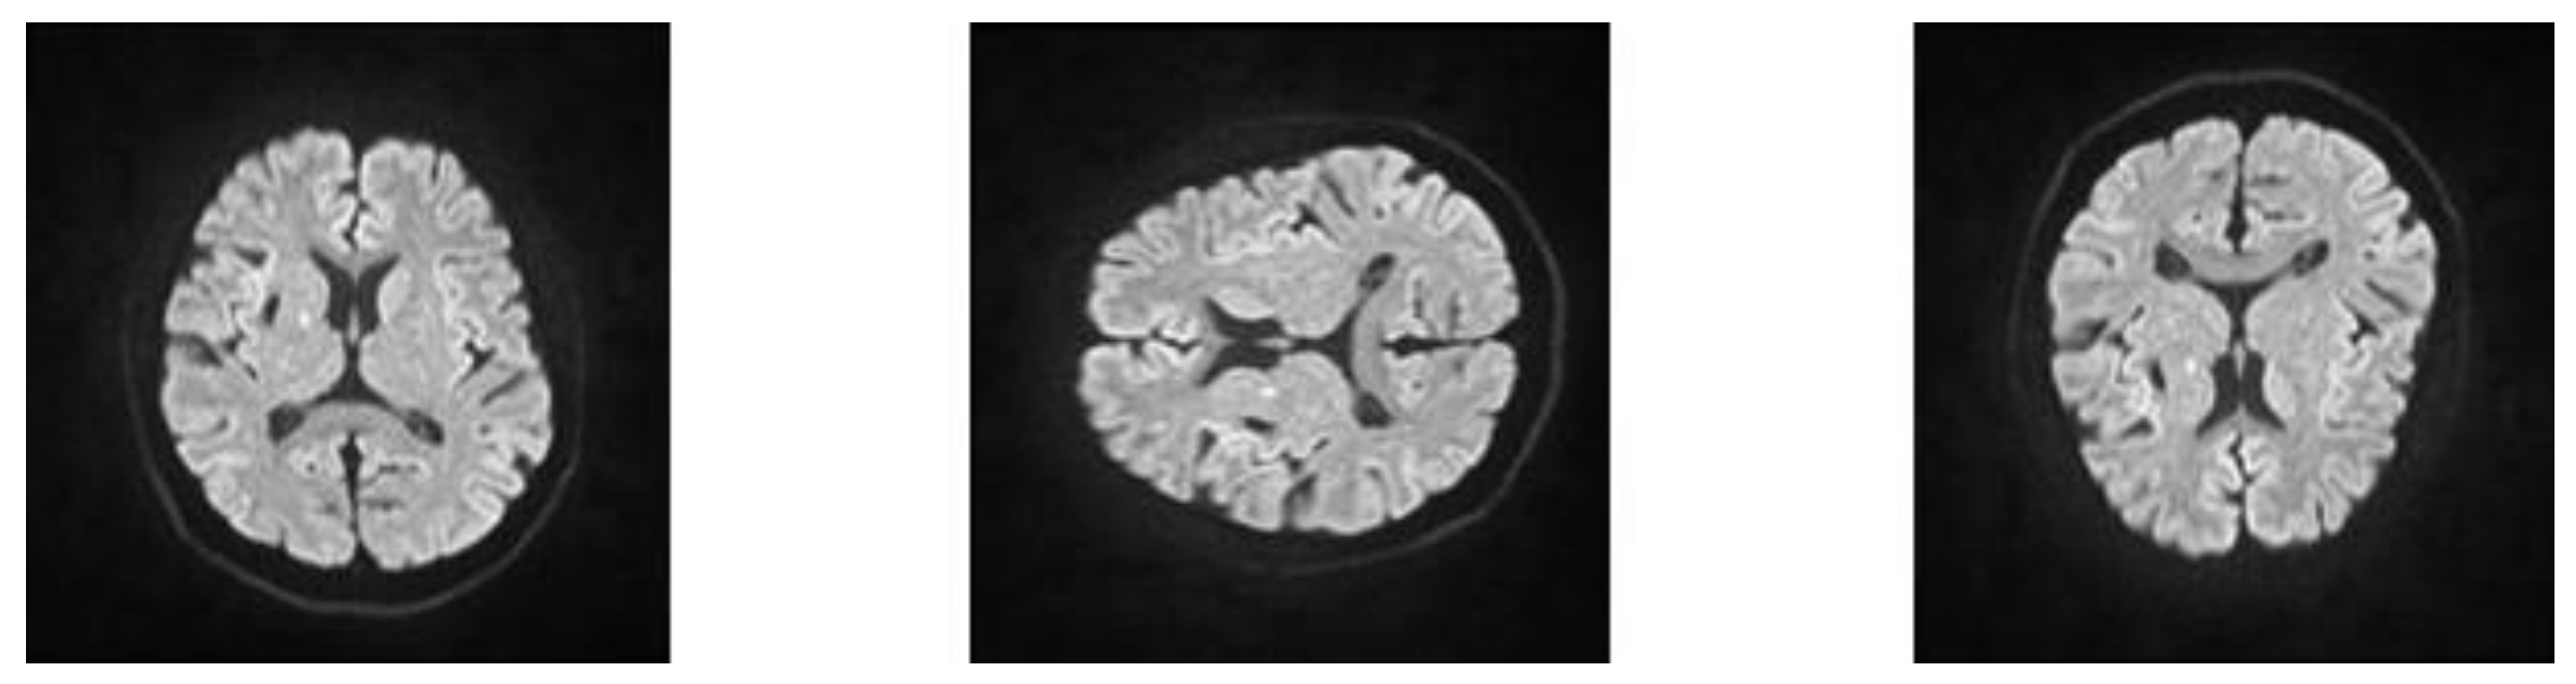

2.2. Imaging Acquisition

2.3. Annotation